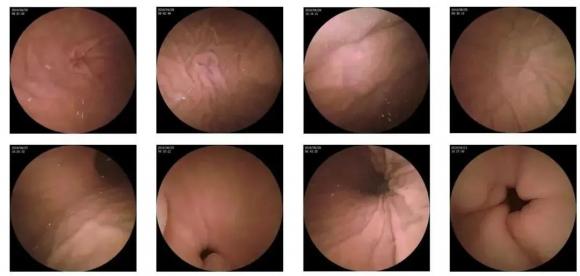

10—15分鐘即可完成賁門、胃底、胃體、胃角、胃竇、幽門等解剖部位觀察,讓胃部檢查更高效。更為重要的是,檢查全程無痛、無創、無麻醉,避免了傳統插管胃鏡帶來的生理痛苦。

膠囊機器人的專利三鏡片鏡頭,可深入觀察0.04毫米微小單位,每秒可拍高達4張高清醫學照片。

任何細微的胃部病變,如胃潰瘍、胃出血、息肉等都無所遁形,盡在磁控膠囊式內窺鏡系統的掌握之中。